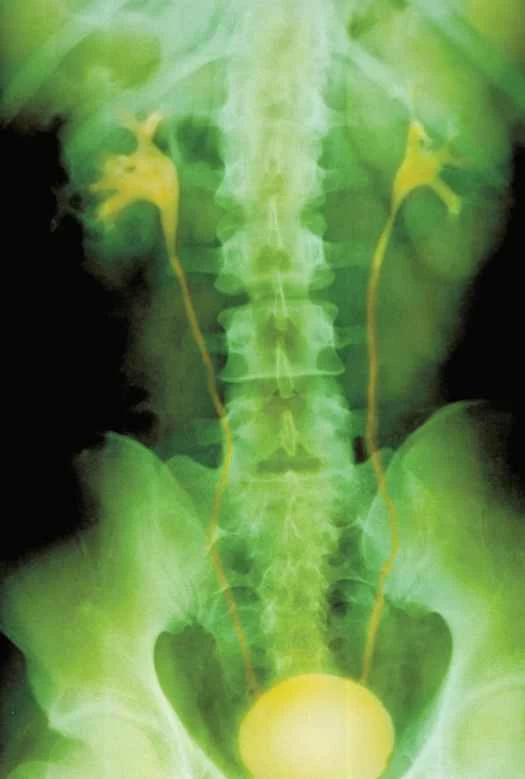

供您參考:膀胱真的會破裂嗎?

只有在特殊情況下才會發生。 「我的意思是,這不會隨便發生在任何一個走在街上憋尿太久的人身上,」芝加哥大學泌尿科醫生斯科特·埃格納說。 「但對於做過大手術、患過癌症、膀胱接受過放射治療,或者膀胱被切除後用腸道組織重建膀胱的人來說,是的——這些情況下膀胱確實可能會破裂。”這些情況會非常痛苦。膀胱破裂時,...